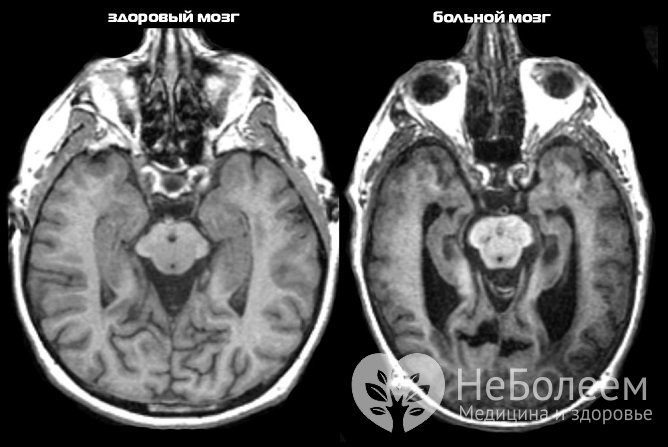

Диагностировать деменцию помогают КТ или МРТОсновными факторами, определяющими стратегию лечения приобретенного слабоумия, являются выраженность клинических проявлений заболевания и его причины. В составе комплексной терапии назначаются: